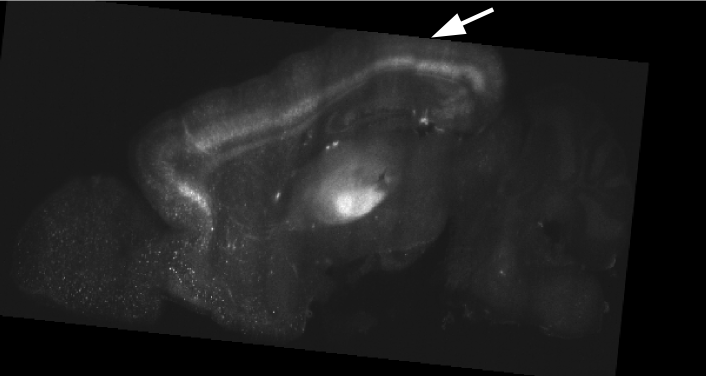

1.6 Challenges

In addition to their large size, CLARITY images present several unique challenges for image registration. In the CLARITY images of this study, a neuron’s brightness is proportional to its activity, which means that CLARITY images have a functional component. Regions which appear bright in one CLARITY brain may appear dark in another (Fig. 3a). Registration is further complicated by brain deformation introduced in the clarifying process (Fig. 3b) and missing data (Fig. 3c).

2.5 Postprocessing

Deformed labels were resampled to a level 5 resolution and fed into the NeuroData cluster. The infrastructure automatically propagated the annotations to higher resolution levels. Thus the full resolution images with ARA labels overlaid could be visualized from a web browser in NeuroDataViz (Fig. 4).